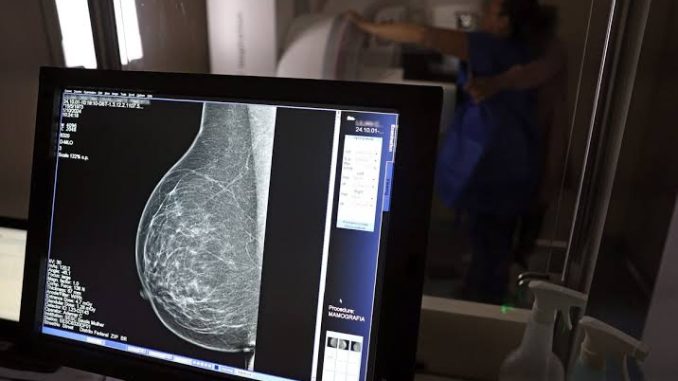

Uma pesquisa realizada pela Universidade de Lübeck, na Alemanha, concluiu que o uso de inteligência artificial (IA) na análise de mamografias pode aumentar a taxa de detecção do câncer de mama sem elevar o número de falsos positivos. O estudo, publicado na revista Nature Medicine, analisou os dados de 461.818 mulheres entre julho de 2021 e fevereiro de 2023, dentro de um programa nacional de rastreamento voltado para mulheres assintomáticas entre 50 e 69 anos. A ferramenta de IA foi utilizada em tempo real, marcando uma diferença significativa em relação a estudos anteriores.

Os resultados mostraram que a IA conseguiu identificar um caso a mais de câncer para cada mil mulheres examinadas, o que representa um aumento de 17,6% na taxa de detecção quando ajustado por fatores como idade. Além disso, a ferramenta emitiu alertas de “rede de segurança” em 3.959 exames que poderiam passar despercebidos por radiologistas, resultando em 204 diagnósticos adicionais. Contudo, a tecnologia apresentou falhas ao deixar de identificar a doença em 20 casos. Ainda assim, o coautor do estudo, Alexander Katalinic, destacou que a IA contribui para a detecção precoce sem causar danos adicionais às mulheres participantes.

Os investigadores acreditam que a tecnologia tem potencial para reduzir a carga de trabalho dos radiologistas ao classificar exames normais e destacar áreas suspeitas. Especialistas, como Stephen Duffy, da Universidade Queen Mary, em Londres, consideraram os resultados impressionantes. No entanto, a implementação exige cautela. Kristina Läng, da Universidade de Lund, na Suécia, ressaltou a importância de acompanhar as implicações clínicas a longo prazo para garantir que a IA detecte casos relevantes de forma precoce e segura.

O estudo reforça o papel promissor da inteligência artificial no combate ao câncer de mama, especialmente na detecção em estágios iniciais. Porém, especialistas alertam que a adoção dessa tecnologia deve ser feita com critérios rigorosos e acompanhamento contínuo para maximizar benefícios e minimizar possíveis riscos.